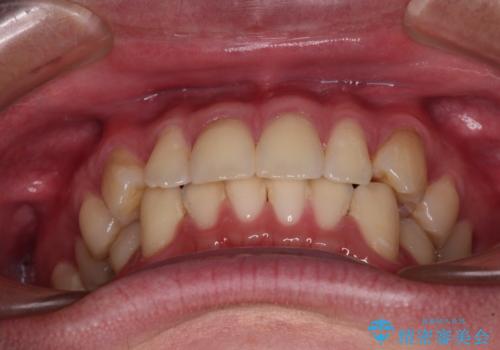

お仕事が忙しく、1日の装着時間は不十分となる日もありましたが、治療は順調に進めていくことができました。

途中、以前大きなむし歯で処置をした歯が痛み出し、根管治療が必要となったため、根管治療とオールセラミッククラウンによる補綴治療を行い、その後にインビザラインによる仕上げの歯列移動を行い、無事に治療を終えることができました。